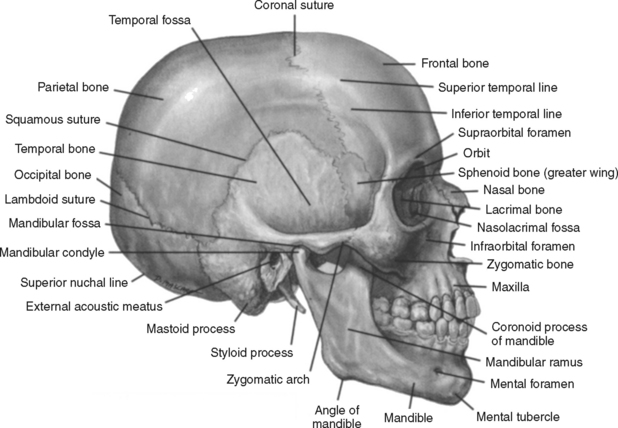

Анатомические особенности: фотографии ямок черепа, височной и подвисочной крылонебной